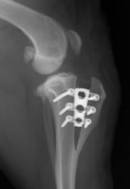

Chirurgia, ortopedia

Wykonujemy szereg zabiegów operacyjnych z zakresu chirurgii miękkiej, jak i twardej. Przeprowadzane przez nas operacje często ratują życie, a niejednokrotnie również polepszają jego jakość.

W przeciwieństwie do wielu gabinetów nasz zespół operuje w składzie 3-osobowym. Jest to niezmiernie ważne, ponieważ ułatwia chirurgowi pracę oraz znacznie skraca czas wykonywania operacji. Dla pacjenta jest to wyznacznikiem profesjonalnie i bezpiecznie wykonanego zabiegu.

Zapewniamy stały nadzór anestezjologiczny i monitoring pacjenta podczas zabiegu oraz opiekę pooperacyjną.

W ramach chirurgii twardej przeprowadzamy m.in. takie zabiegi jak:

• operacje stawu kolanowego po uszkodzeniu więzadła krzyżowego

• zwichnięcie stawu biodrowego, w tym resekcja główki i szyjki kości udowej

• zwichnięcia rzepek

• operacyjne leczenie złamań i zwichnięć